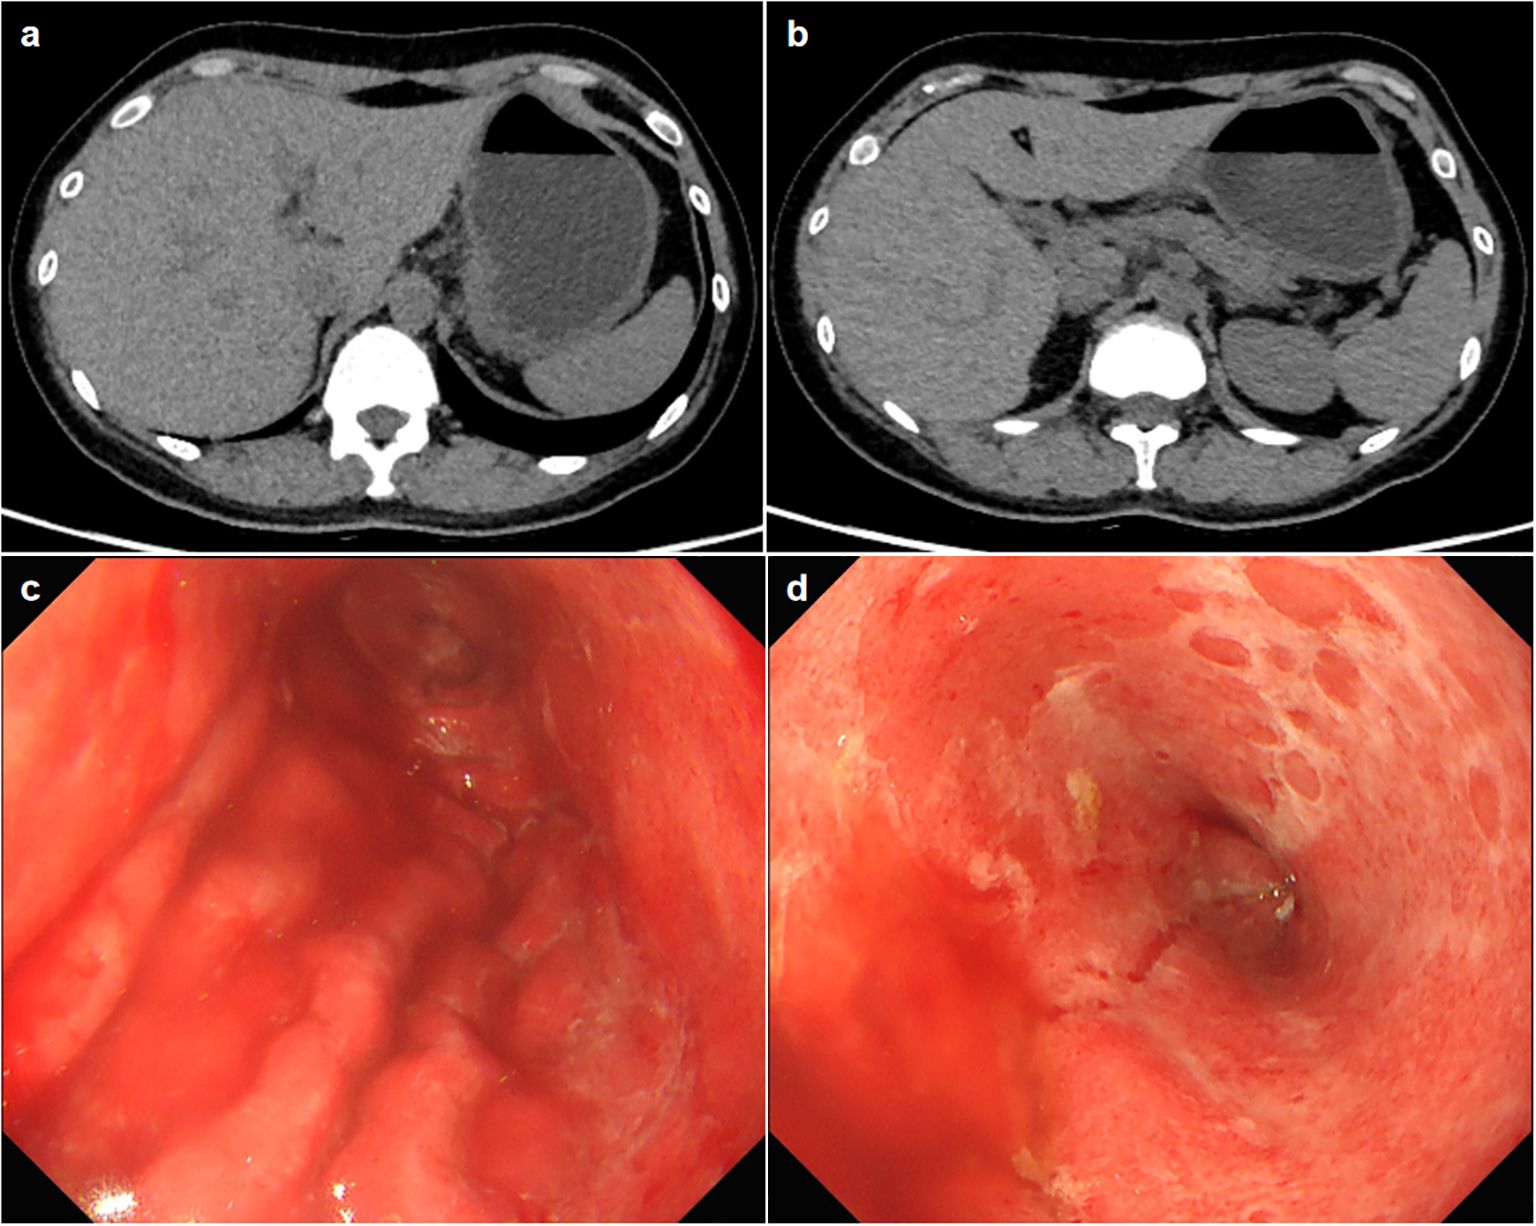

Physical examination showed vital signs were stable, only slight tenderness in the upper abdomen, but no rebound pain. Laboratory tests showed elevated alanine aminotransferase (161U/L, normal range 7–40 U/L), aspartate transaminase (222U/L, normal range 13-35U/L), Gamma-Glutamyl Transpeptidase (552U/L, normal range 7-45U/L), Alkaline phosphatase (546U/L, normal range 35-100U/L) and amylase in blood (249U/L, normal range 28-100U/L). Her blood sample was also tested positive for anti-Epstein-Barr(EB) virus chlamydial antigen(VCA) IgG and anti-EB virus nuclear antigen IgG, and an elevated concentration of EBV DNA (1.04×104, normal value <4×102 copies/ml) was detected. The complete blood count, C-reactive protein (CRP) and carcinoma embryonic antigen levels were normal. She tested negative for human immunodeficiency virus (HIV). Abdominal computed tomography did not demonstrate thickening of the gastric wall or enlarged lymph nodes in the abdominal cavity (Figures 1A, B). Magnetic resonance cholangiopancreatography showed a slight widening of the upper part of the common bile duct with a tortuous course, but no definite obstruction was found. The first look of her esophagogastroduodenoscopy in our hospital is as shown in Figures 1C, D. Endoscopic biopsy of the stomach suggested that the vast majority of glandular components disappeared and were replaced by inflammatory granulation tissue, with lymphocytes and eosinophilic granulocytes infiltration. Immunohistochemistry showed that CD3, CD4 and CD8 were positive. Rapid urease test of the stomach tissue was positive; The Epstein-Barr encoding region in situ hybridization suggested scattered positive. Cytomegalovirus was not found in the stomach tissue.

Figure 1. (A, B) Axial slice of computed tomography showing no thickening of the gastric wall or enlarged lymph nodes. (C, D) The esophagogastroduodenoscopy images show a widespread exfoliation of the gastric mucosa.